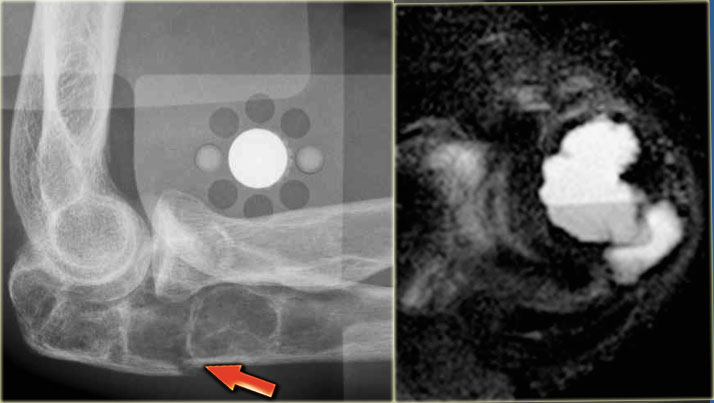

Here images of a 30-year-old male.

There is a wel-defined lytic lesion of the olecranon with several ridges and a pathologic fracture.

The differential diagnosis includes giant cell tumor and ABC.

The T2WI+FS shows fluid-levels due to sedimentation making ABC the most likely diagnosis.

Biopsy however revealed Brown tumor.